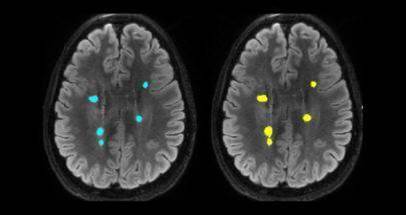

Another tool being developed for use in research and clinical trials aims to help image analysts accurately determine the size of brain lesions - either to see how they progress over time or respond to different treatments.

Analysts typically segment the 3D images of brain lesions manually to determine their volume, a process which can take up to 15 minutes.

The measurements are sometimes guessed from ‘eyeballing’ the scans due to how long it takes to determine the size of the irregularly shaped structures. Meanwhile, SNAC’s algorithms can reduce that time to three seconds while also delivering more accurate results.